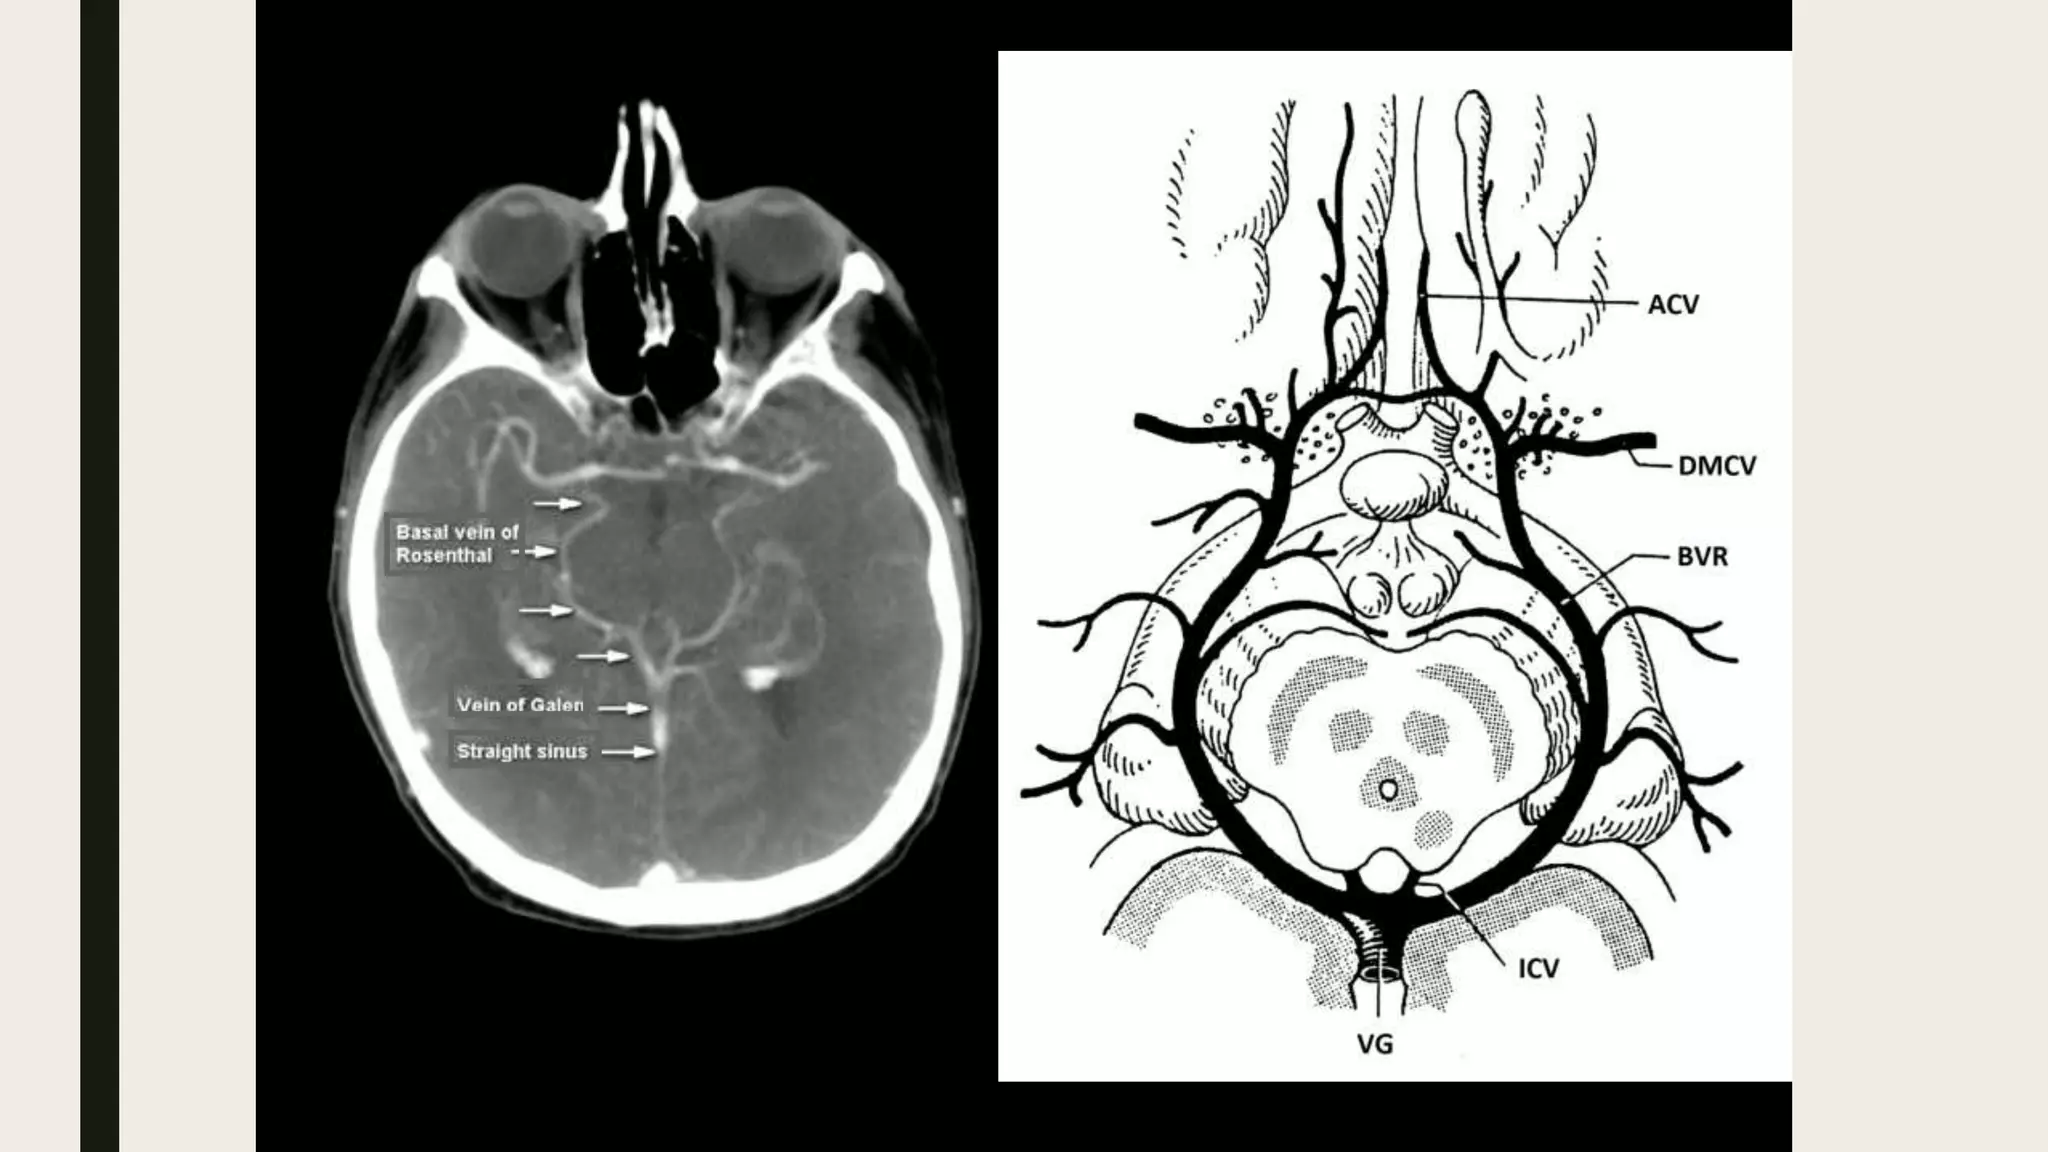

• P2 segment of PCA.

• Superior cerebellar artery.

• Anterior choroidal artery.

• Basal vein of Rosenthal.

Contents

• Basal vein of Rosenthal .